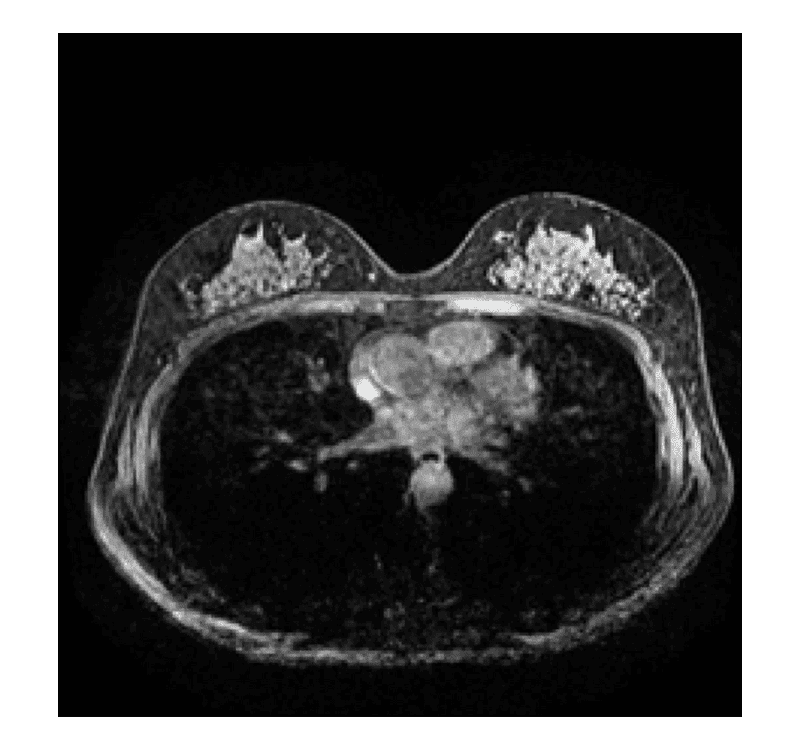

乳房MRI

うつぶせの姿勢で乳房を挟まず左右一度に撮影する検査です。腫瘤の発見や病変の広がり、乳房左右差の比較などを得意とします。日本人に多いとされているデンスブレスト(高濃度乳腺)に対して、がんを検出する精度が高いといわれています。